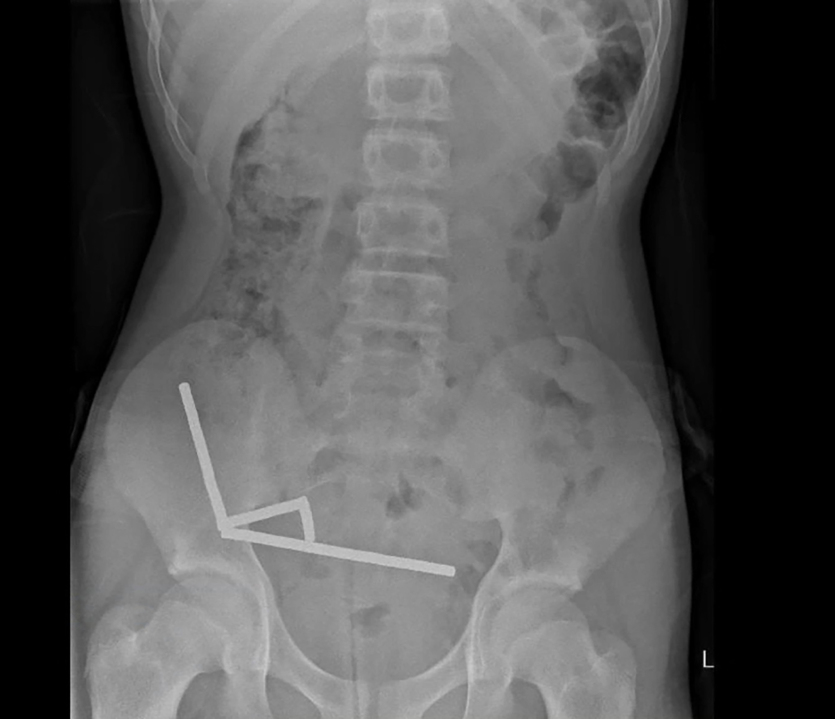

Après avoir souffert de douleurs abdominales pendant quatre jours, un adolescent de 13 ans a été transporté à l’hôpital de Tauranga, sur l’île du Nord. "Il a avoué avoir ingéré entre 80 et 100 aimants puissants au néodyme, de 5x2mm environ, une semaine plus tôt", indique un rapport des médecins de l’hôpital de cet hôpital, publié ce vendredi 24 octobre dans le New Zealand Medical Journal (NZMJ). Ce type d’aimants, interdit en Nouvelle-Zélande depuis janvier 2013, aurait été acheté sur la plateforme chinoise d’e-commerce Temu.

Les médecins ont déclaré que la pression exercée par les aimants avait provoqué une nécrose dans quatre zones de l’intestin grêle et du gros intestin du garçon. Il a été opéré afin que l’on lui retire les aimants et les tissus nécrosés, et il a pu rentrer chez lui après huit jours à l’hôpital.